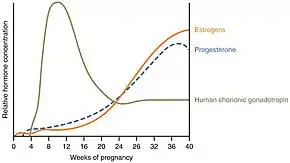

Psychological

During the later stages of gestation there is an increase in abundance of oxytocin, a hormone that is known to evoke feelings of contentment, reductions in anxiety, and feelings of calmness and security around the mate.[25] Oxytocin is further released during labour when the fetus stimulates the cervix and vagina, and it is believed that it plays a major role in the bonding of a mother to her infant and in the establishment of maternal behaviour. Studies show that the father of the child also has an increase in oxytocin levels following contact with the infant and parents with higher oxytocin levels showed more responsiveness and synchrony in their interactions with their infant. The act of nursing a child also causes a release of oxytocin to help the baby get milk more easily from the nipple.[26][27]

It has long been known that a mother's level of the hormone oxytocin elevates in a mother when she interacts with her infant. In 2019, a large review of the effects of oxytocin found that the oxytocin level in fathers that engage in SSC is increased as well. Two studies found that "when the infant is clothed only in a diaper and placed in between the mother or father's breasts, chest-to-chest [elevated paternal oxytocin levels were] shown to reduce stress and anxiety in parents after interaction."[70]

Augmentation

Augmentation is the process of stimulating the uterus to increase the intensity and duration of contractions after labour has begun. Several methods of augmentation are commonly been used to treat slow progress of labour (dystocia) when uterine contractions are assessed to be too weak. Oxytocin is the most common method used to increase the rate of vaginal delivery.[106] The World Health Organization recommends its use either alone or with amniotomy (rupture of the amniotic membrane) but advises that it must be used only after it has been correctly confirmed that labour is not proceeding properly if harm is to be avoided. The WHO does not recommend the use of antispasmodic agents for prevention of delay in labour.[107]